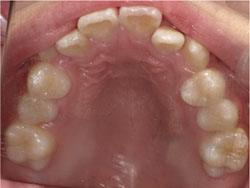

1期治療でスケルトンタイプの拡大装置で歯列拡大後、歯も抜かずにきれいになりました。

矯正前

矯正中

矯正終了後